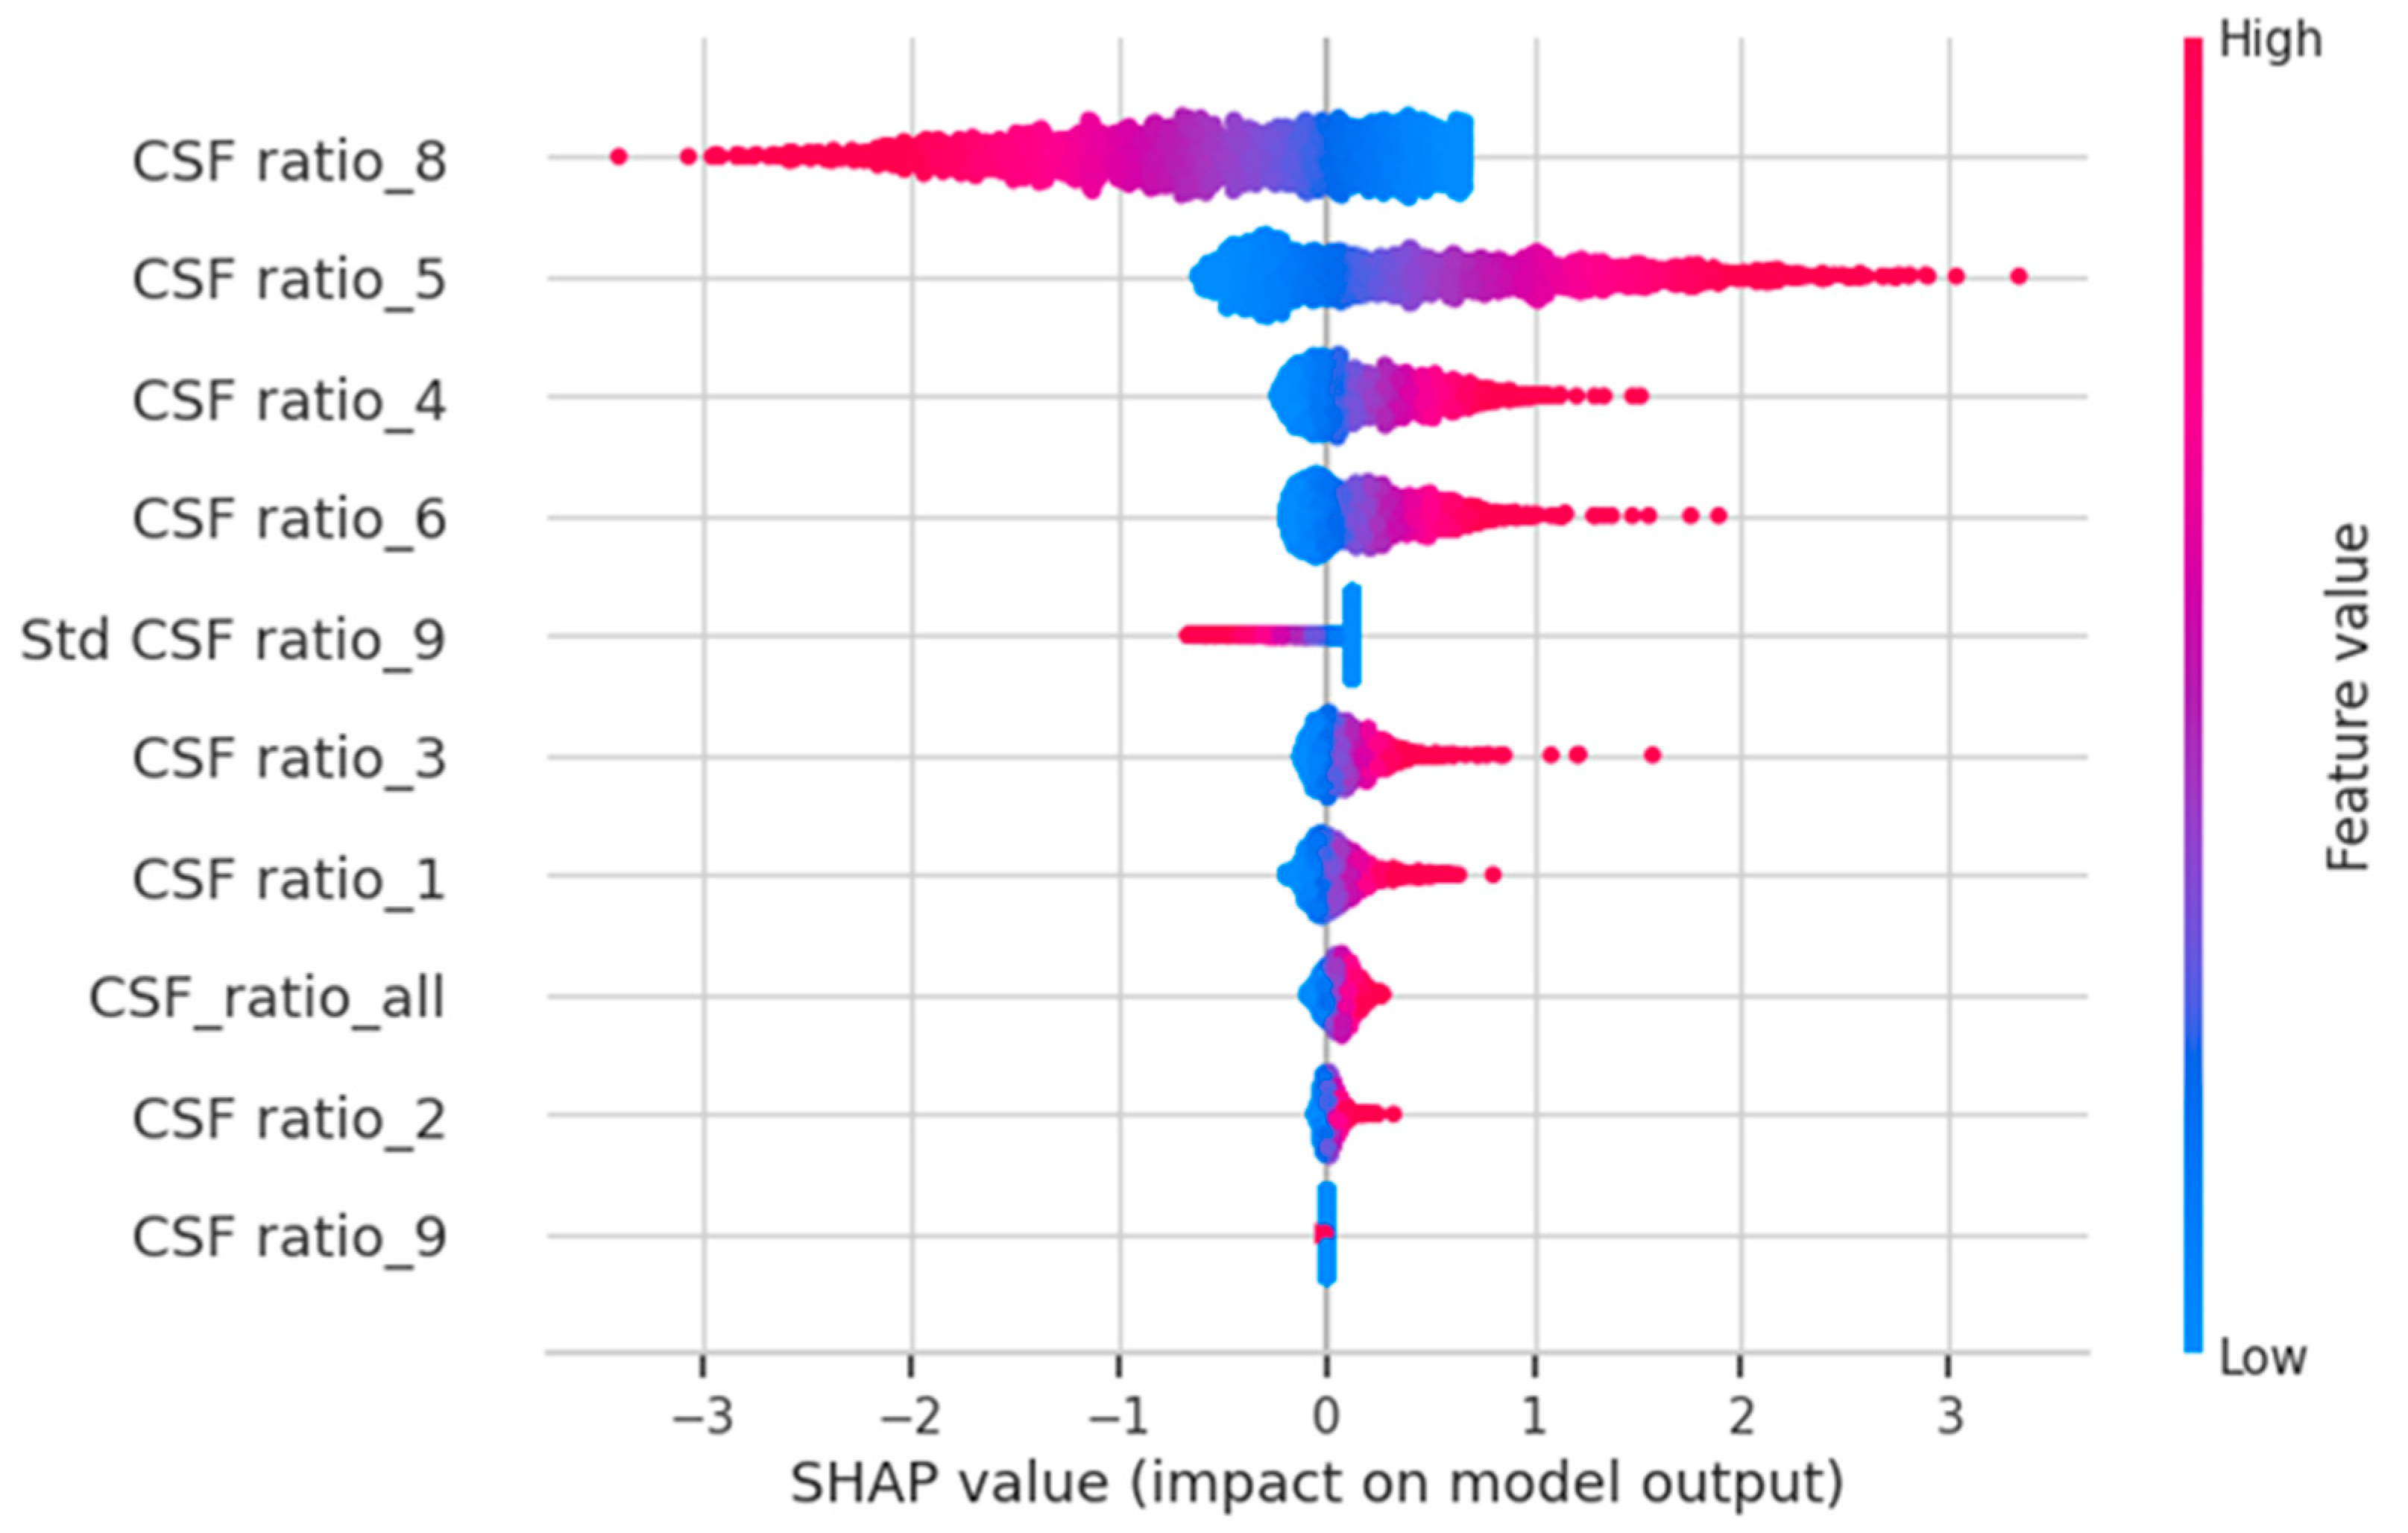

2.4. AI Evaluation